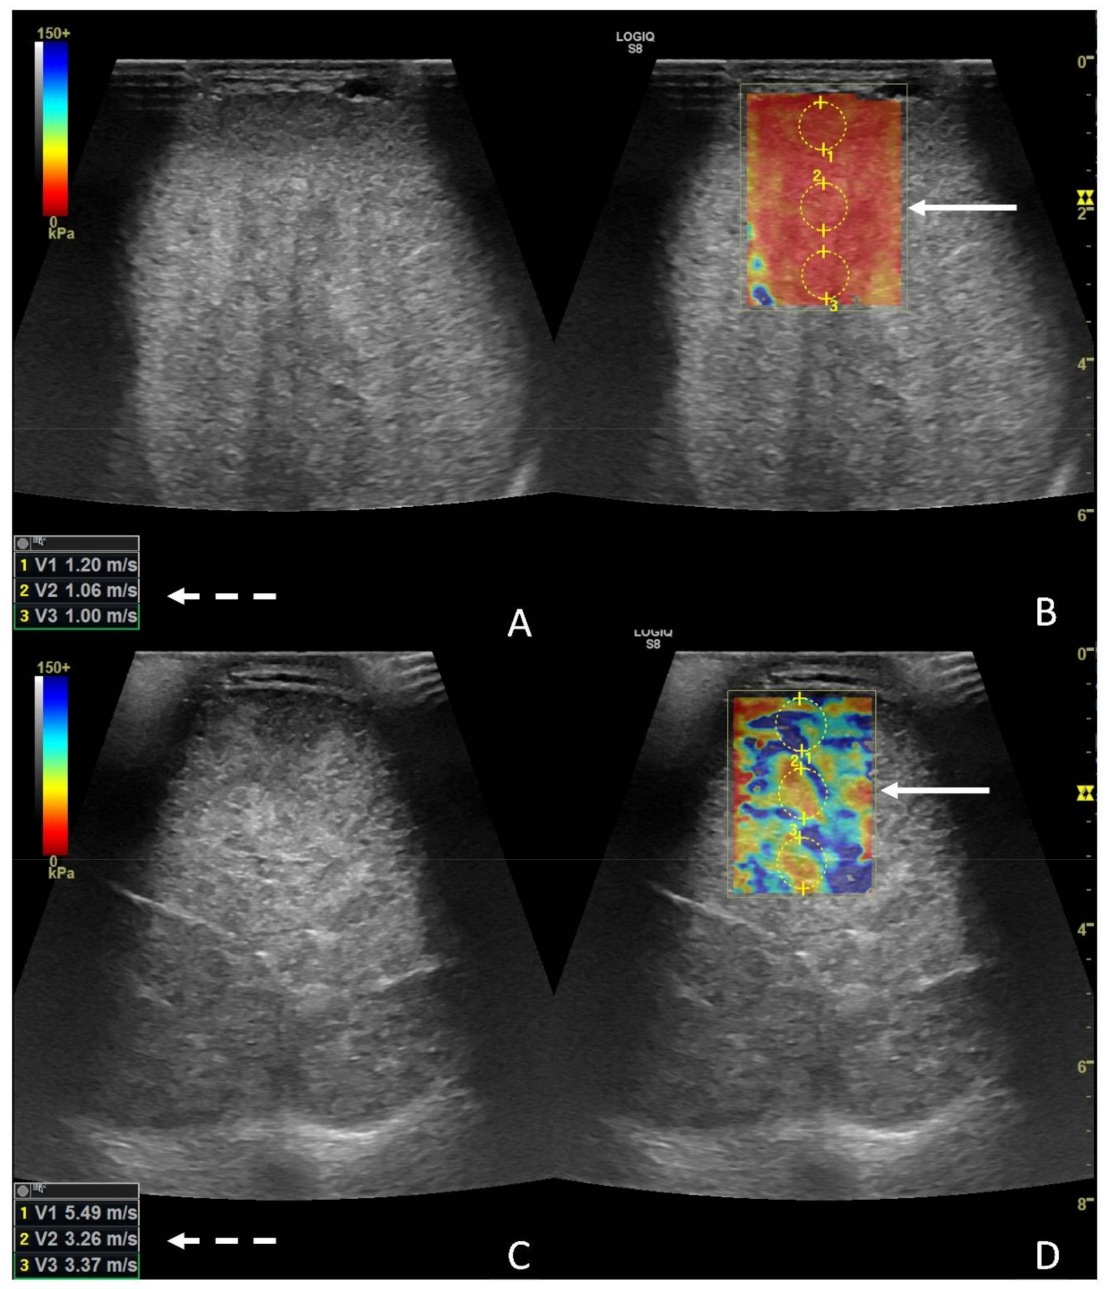

The right testicle was characterized using central parenchymal red-green color with blue edges and without red bands (Figure 5A,B), while the left one was characterized by a heterogeneous appearance, predominantly classifiable as 5, mostly in the central areas, with some areas with 1 and 2 scores localized more peripherally (Figure 5C,D).

Regarding 2D-SWE, the left testicle was globally significantly stiffer (p < 0.0028) than the contralateral, with a median value for the left testicle of 3.66 m/s (1.8–6.64), and median values for the right testicle were 1.15 m/s (0.8–1.6) (Figure 6A–D).

Figure 6. Images from 2D-SWE of a normal (A,B) and a diseased testicle (C,D). In panels A and B, the B-mode image and the elastogram are presented, respectively; the white dotted arrow points at the values from the ROIS manually drawn on the elastogram (white solid arrow). In panels C and D, a B-mode image and elastogram are presented as well; notice the higher values (white dotted arrow) from the ROIS pointed on the elastogram (white solid arrow).